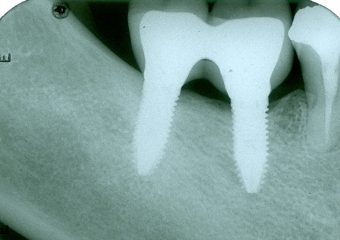

Raio X dos implantes instalados

Raio X final